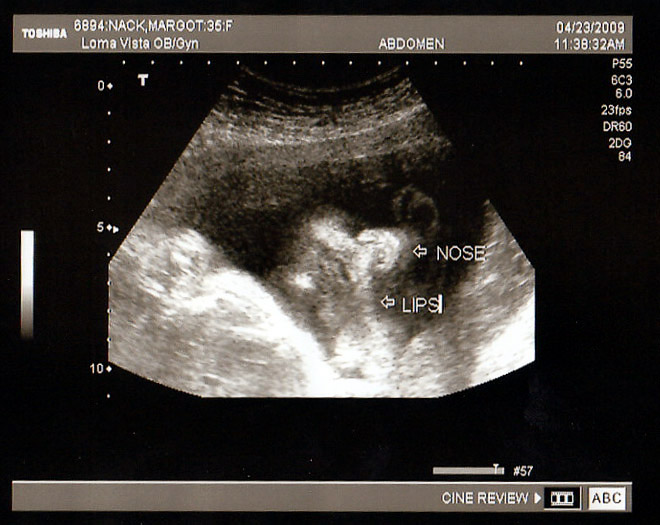

John & Margot Nack